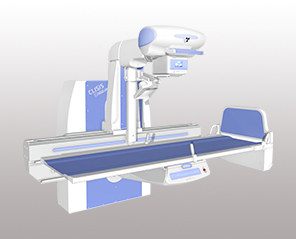

کمپانی General Medical Merate S.p.A. یا همان GMM فعالیت خود را از سال ۱۹۵۲ آغاز کرده و در حال حاضر، یک هلدینگ مطرح در جهان است. تولیدات این کمپانی ایتالیایی شامل دستگاه فلوروسکوپی، رادیولوژی دیجیتال، ماموگرافی دیجیتال، ایکسری پرتابل، C-arm و تخت جراحی C-arm است. برخی برندهای مطرح مانند MT-MEDICAL TECHNOLOGY، MECALL، MERATE POWER، PRIMAX، D/VISION LAB و IMS GIOTTO زیر مجموعه این هلدینگ هستند.

همکاری گروه تجهیزات پزشکی رئوف با این کمپانی، از سال ۱۳۹۲ آغاز شد و ما نیز در راستای تحقق این اهداف در مرزهای خود کوشیدهایم و خرسندیم که تا به امروز، با نصب دستگاههای رادیولوژی و ماموگرافی GMM، بسیاری از مراکز درمانی را با سیستم پیشرفته این دستگاهها تجهیز کردهایم.